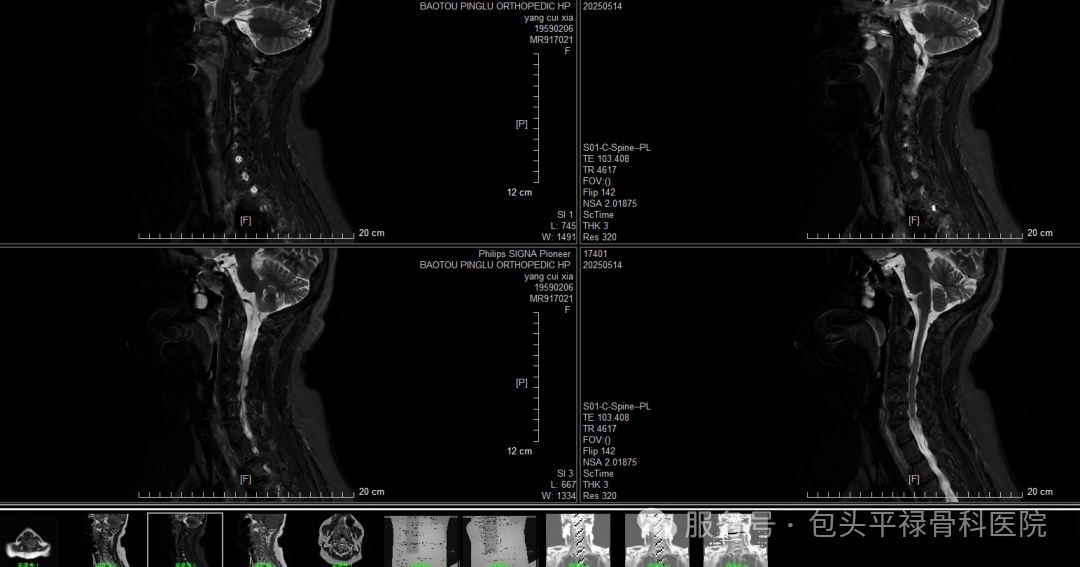

DR-CT-MRI影像对比

图源:包头平禄骨科医院

MRI:软组织“透视镜”,精密无辐射

MRI,即磁共振成像,其工作原理是通过磁共振设备,让人体中的氢原子产生共振,再平静下来,根据振动和平静之间的能量差进行成像,观察正常组织与患病部位之间的能量信号差异。对于软组织、肌肉组织、神经组织的探索能力较强。

检查应用范围

适用于全身部位及多种疾病的检查、诊断,对脊柱、关节、肿瘤、淋巴结和血管结构的相互识别具有独特优势。骨科方面,对于椎间盘突出、肩袖损伤、膝关节韧带及半月板损伤等疾病的检查,医生们更倾向于优先选择MRI。

优点:软组织显示清晰,能多维度提供病灶信息;没有骨性伪影,无辐射

缺点:费用高、检查时间较长、不适用于体内留有金属物品者